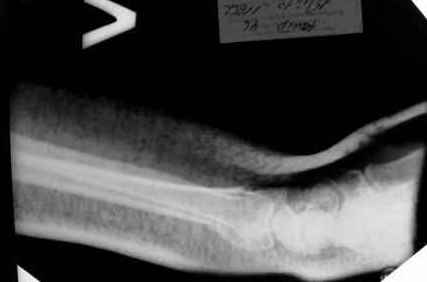

Дальнейшее лечение консервативное. Через 6 недель- гипс снят,

назначено ЛФК. Пациентка крайне недовольна.

Говорит, что на снимке у нее выступает кость, я ей сломал руку и.т.д. В общем началось.

Пациентка прочитала в интернете наверное все, что есть по данной травме. По заключениями

рентгенологов и консультанта из КДЦ областной больницы- стояние отломков допустимое.

Объективно говоря- снижена высота лучевой кости, диастаз лучелоктевого сочленения, и не

сросся шиловидный отросток. однако на РКТ при сравнении с другой стороной- разница

незначительная.

Что на снимках при снятии гипса- сам вижу.